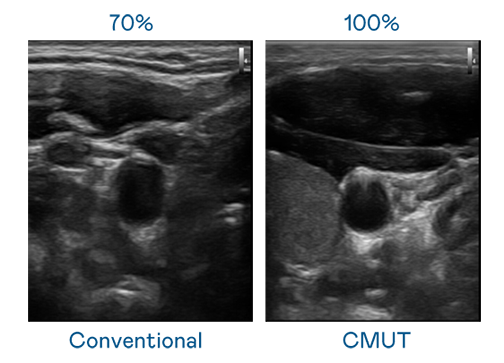

CMUT 技术是一种用电容式微机电元件来产生超音波讯号的技术。与传统 PZT 压电式技术相比,CMUT 频宽增加 30%,更宽频的超音波讯号让影像解析度大幅提升,是实现高影像品质医疗超音波扫描、促进精准医疗发展的关键技术。

超音波影像的解析度高低,首先取决于探头能发出的讯号频宽。伟德国际1949 CMUT 可提供高清晰的超音波讯号,提供高频宽、高灵敏度、影像纹理细节更高的超音波影像,协助医护人员缩短影像判读时间及利用精准的医疗影像进行诊断。